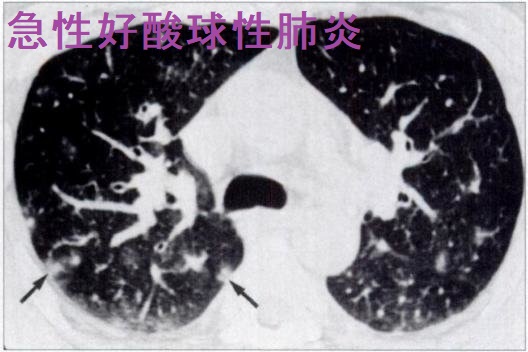

急性好酸球性肺炎

急性好酸球性肺炎(acute eosinophilic pneumonia)慢性好酸球性肺炎は病態が全く異なり、別物と考えられています。急性好酸球性肺炎は、喫煙開始の早期に発症することが多い原因不明の肺炎です。受動喫煙(副流煙)でもおこります。アレルギー素因との関連は明らかでないが、タバコ煙やタバコの吸い口部分に含まれる化学物質に対するアレルギー反応と考えられます。急性好酸球性肺炎は20 ~30 歳代に好発し、男女比2:1で男性に多い。

急性好酸球性肺炎では

2. 胸部CT;両側びまん性のすりガラス陰影・小葉間隔壁の肥厚・浸潤影

胸水貯留(片側性もしくは両側性)

3. 気管支肺胞洗浄液中の好酸球数増加(好酸球が25%以上)

4. 肺生検で確定診断;著明な好酸球浸潤

[AJR Am J Roentgenol. 1996 Nov;167(5):1195-9.]